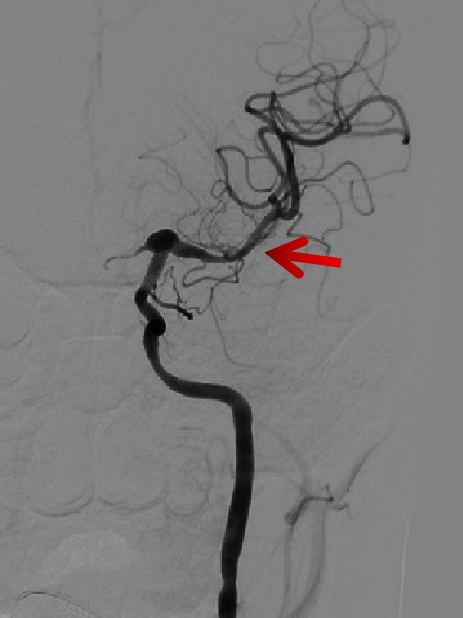

造影显示:左侧A1段血流纤细,左侧前循环供血通过右侧A1段及前交通代偿。

左侧颈内动脉末端梭形夹层动脉瘤,2.9mm*3.5mm。